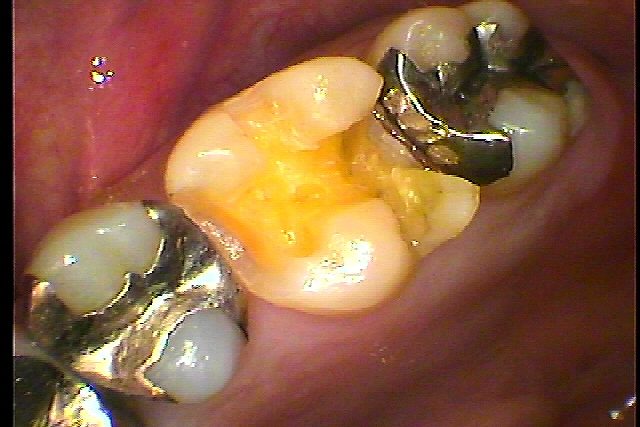

左上6番の銀歯が取れた診てほしい 食事をしていたらいきなり取れた。|お知らせ |広島市安佐南区の歯科医院 左上6番の銀歯が取れた診てほしい 食事をしていたらいきなり取れた。 トップ お知らせ・ブログ お知らせ 左上6番の銀歯が取れた診てほしい 食事をしていたらいきなり取れた。 左上6番の銀歯が取れた診てほしい 食事をしていたらいきなり取れた。 取れた歯になります このように中はむし歯になっています 隣接部も虫歯でした 近心部にも虫歯が波及 隣接部も含めて虫歯を除去しました セレックプライムスキャンにてこのようにきれいに仕上げています Web診療予約 初めての方へ 選ばれ続ける理由 院内設備について 歯が痛いしみる一般歯科 歯がぐらぐらする歯周病 健康な歯を保ちたい予防歯科 子供の虫歯予防をしたい小児歯科 銀歯をセラミックに審美歯科 白い歯を目指しませんか?ホワイトニング 矯正専門医がいるので安心矯正歯科 抜けた歯を補いたいインプラント・入れ歯 医院案内 スタッフ紹介 メリィハウス歯科クリニックオフィシャルホームページ ラベンダー歯科クリニックオフィシャルホームページ お知らせ・ブログ ホーム 診療科目 一般歯科 歯周病治療 予防治療 小児歯科 審美治療 ホワイトニング 矯正歯科 入れ歯・インプラント マウスピース矯正 初めての方へ 院長・スタッフ 設備紹介 医院案内・アクセス メニューを閉じる